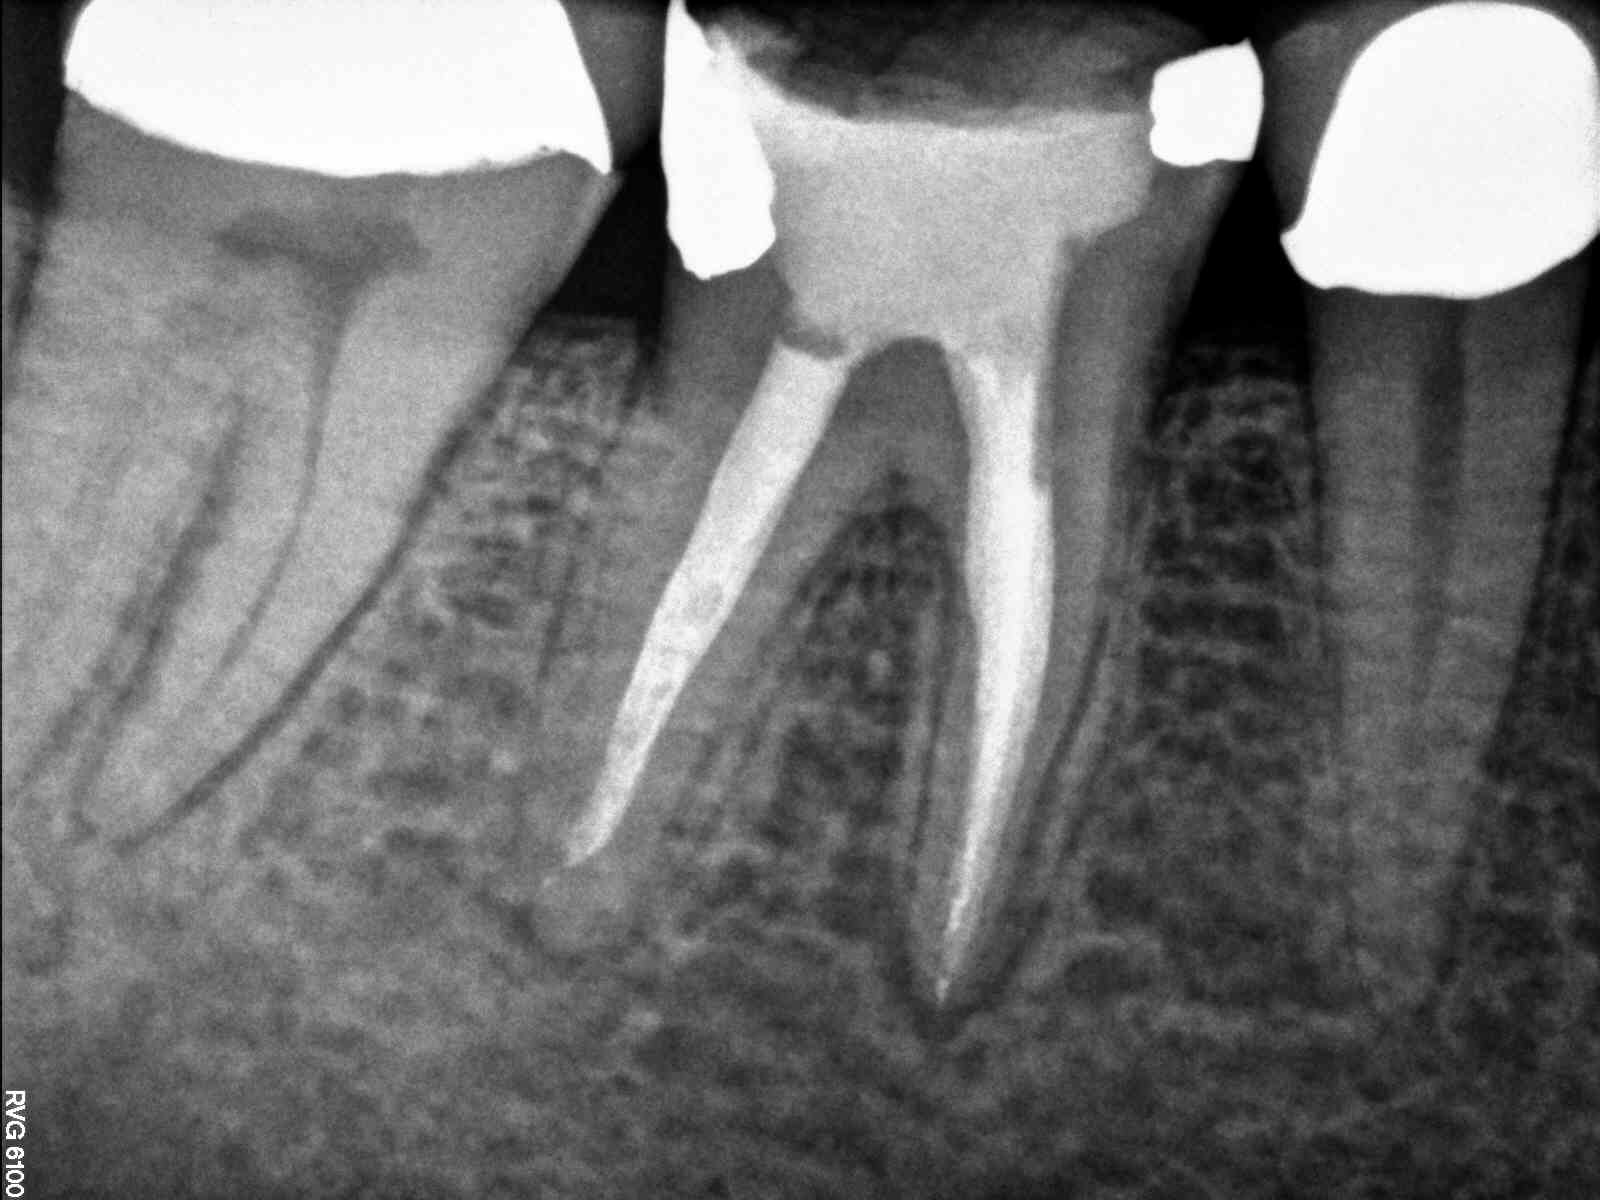

| Xray taken from distal so ML and mid-mesial on left. |